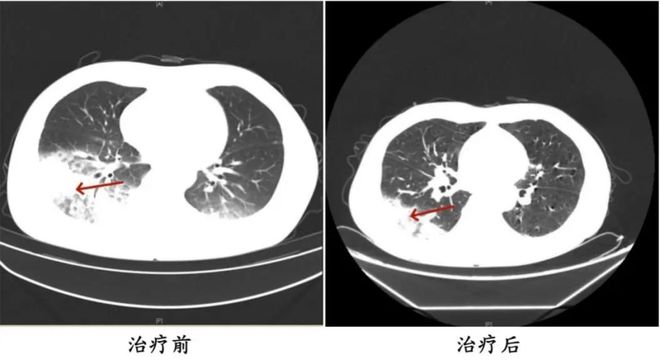

前不久,55岁的湖南长沙市民周益(化名)既往有2型糖尿病、2型糖尿病性肾病、慢性肾功能不全等多个病史,近日因持续发热、寒战、咳嗽4天,在长沙市中心医院就诊后住院接受治疗。

医生在检查中发现,患者的肺部存在严重感染,多项感染指标明显升高。应用抗生素抗感染治疗后效果不佳,患者依然持续发热,还出现了神志淡漠的异常表现。